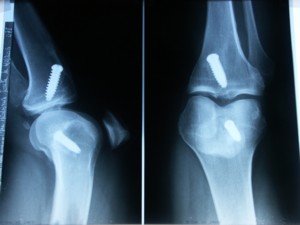

Le genou de Josette est entré en collision avec la tête de Sylvestre. Le médecin craignait une fêlure, mais ce n'est heureusement pas le cas; il y a quand même un hématome et un épanchement pré-rotulien (ce n'est pas pédant, c'est précis). Sur la radio ci-dessous, les vis sont celles de l'opération des ligaments croisés d'il y a deux ans.